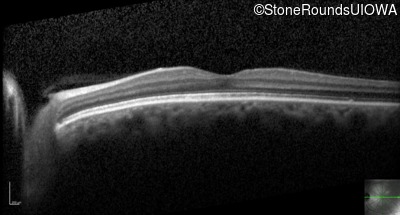

Optical Coherence Tomography - Right - 20/200

Exemplar / OCT Stack

OCT Stack